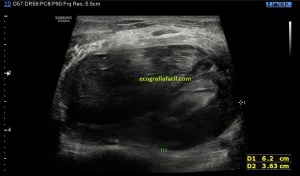

En este breve post te voy a presentar unas imágenes muy bonitas de una vesícula, en una paciente que acude a la cita de ecografía por sospecha de patología a ese nivel, con molestias anodinas e inespecíficas en el contexto de un estudio de su especialista de digestivo.

Observa las imágenes y luego te explico los hallazgos:

Cuando hice el corte longitudinal de la vesícula pude ver hasta tres patologías distintas, una adeomiomatosis (sin artefacto en cola de cometa), una litiasis vesicular y barro biliar, 2,3 y 4 respectivamente.

El caso no tiene mucho que explicar a no ser por la rareza de que se presente triple la semiología patológica en una misma imagen.

La adenomiomatosis, como un aumento de la ecogenicidad y el tamaño de la pared vesicular, la litiasis como una estructura hiperecogénica con sombra acústica posterior y el barro biliar, hiperecogénico rellenando toda la estructura ovoidea de la vesícula.

El cuello vesicular estaría afectado por la adenomiomatosis, el cuerpo por la litiasis y el barro ocuparía el fundas vesicular.